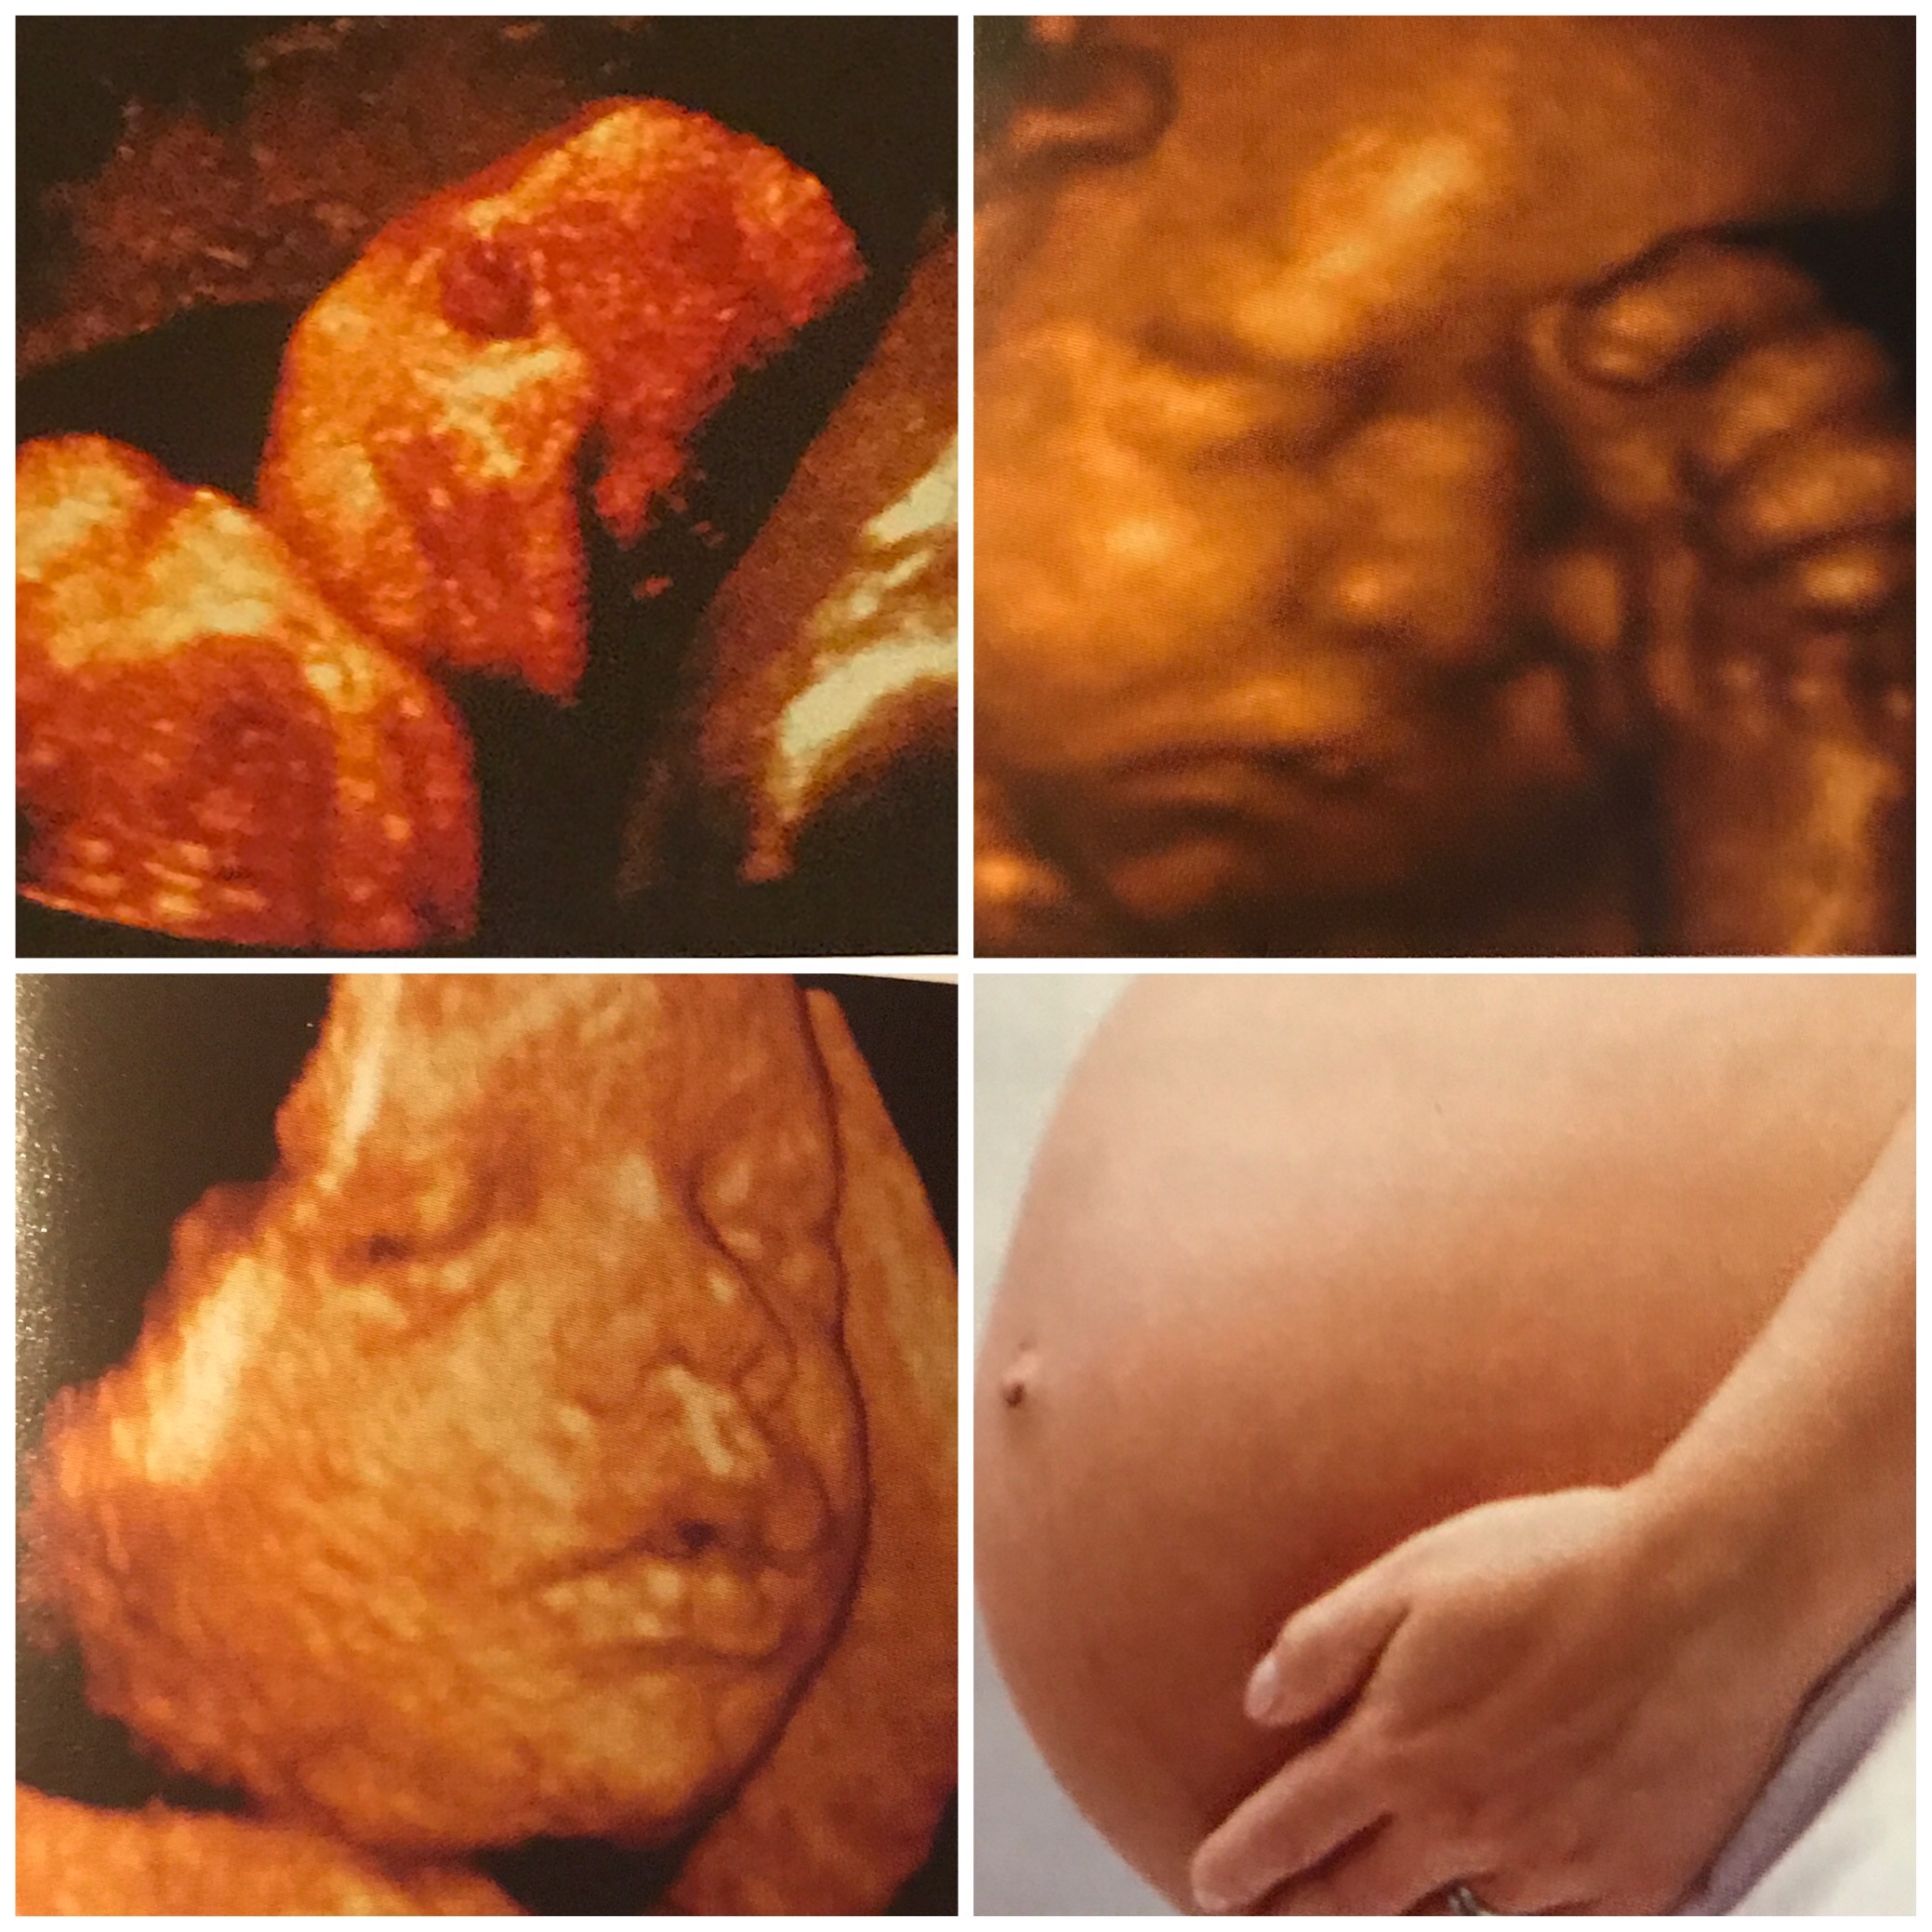

This week our baby is an estimated size of 16 and a half inches and 3 1/3 pounds, compareale in length stalks of asparagus. For another size comparison, I put the asparagus near a bread pan.

This week baby can turn his or her head for the first time and fat deposits are accumulating in his or her legs or arms. Baby Center predicts more arm and leg movement will be felt and that is certainly true today.

I found the photos in “Youe Pregnancy Day by Day” very relevant to our baby’s development. S/he had both hands up to his or her face for the growth scan, and similarly the pictured baby had one hiding his for or her face. The clear face photo on the bottom shows black space like many of our 3D photos did.

The belly button photo shows that for many women this week is one in which their belly button has one will pop out. Though mine seems more shallow than it as prepregnancy, I still have the innie one overall I’ve had my whole life.